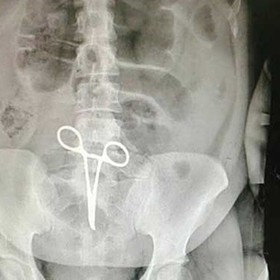

مدیر روابط عمومی دانشگاه علوم پزشکی اصفهان گفت: در خصوص اشتباه پزشکی در یکی از بیمارستانهای اردستان این احتمال وجود دارد که پنس زیر رودهها باقی مانده باشد.

کیانوش جهانپور در گفتوگو با ایسنا و با اشاره به جا ماندن یک پنس در بدن بیمار اردستانی، اظهار کرد: این اتفاق قصور پزشکی است، اما اظهار نظر دقیق در رابطه با آن در صلاحیت سازمان نظام پزشکی است. این اتفاق یا قصور پزشک، یا قصور تکنسینهای اتاق عمل و یا بنا بر شرایط قصور هردو است. این موضوع بستگی به محتویات پرونده بیمار و اتفاقاتی دارد که در اتاق عمل رخ داده است.

وی با اشاره به اینکه در برخی از عملها دهها پنس برای کاربردهای مختلف در بدن بیمار استفاده میشود ادامه داد: برای مثال ممکن است پزشک برای بستن موقت برخی از رگها یا نگاه داشتن اندام داخلی در وضعیتی ثابت و یا نشانهگذاری در بدن بیمار از انواع پنس استفاده کند. پزشک باید هنگام قرار دادن پنس در بدن بیمار با تکنسین اتاق عمل هماهنگ باشد تا شمار پنسهای موجود در بدن بیمار مشخص باشد.

مدیر روابط عمومی دانشگاه علوم پزشکی اصفهان افزود: بعد از اتمام فرایند عمل ممکن است پنس در زیر رودهها قرار گرفته و دیده نشده باشد. این وظیفه پرسنل اتاق عمل است که تعداد پنسهای خارج شده از بدن بیمار را کنترل کنند تا هیچ پنس و وسیلهای در بدن بیمار جا نماند. در انتهای عمل و قبل از اینکه جراح شکم را ببندد همواره سؤال میکند که چه تعداد وسیله داخل بوده و چه تعداد بیرون آورده شده است.

جهانپور تأکید کرد: این اتفاق قصور است، اما باید توجه کرد در همه جای دنیا با وجود همه فرایندهایی که برای جلوگیری از این اتفاق طراحی شده است باز هم اتفاق میافتد. اما در هر حال این اتفاق قصور است. در هر حال به منظور تلطیف فضا، این بیمار به صورت رایگان مورد عمل جراحی قرار گرفته و وضعیت او در حال حاضر ثابت است و بیمار مشکلی نداشته و خطری وی را تهدید نمیکند.

به گزارش ایسنا؛ گرچه بیمار به صورت رایگان عمل شده است، اما بر اساس قانون بیمار در این حالت باید هزینه کامل خارج کردن پنس از شکم خود را پرداخت کرده و پس از طی مراحل شکایت از پزشک و کادر اتاق عمل این هزینه را در قالب خسارت دریافت کند.